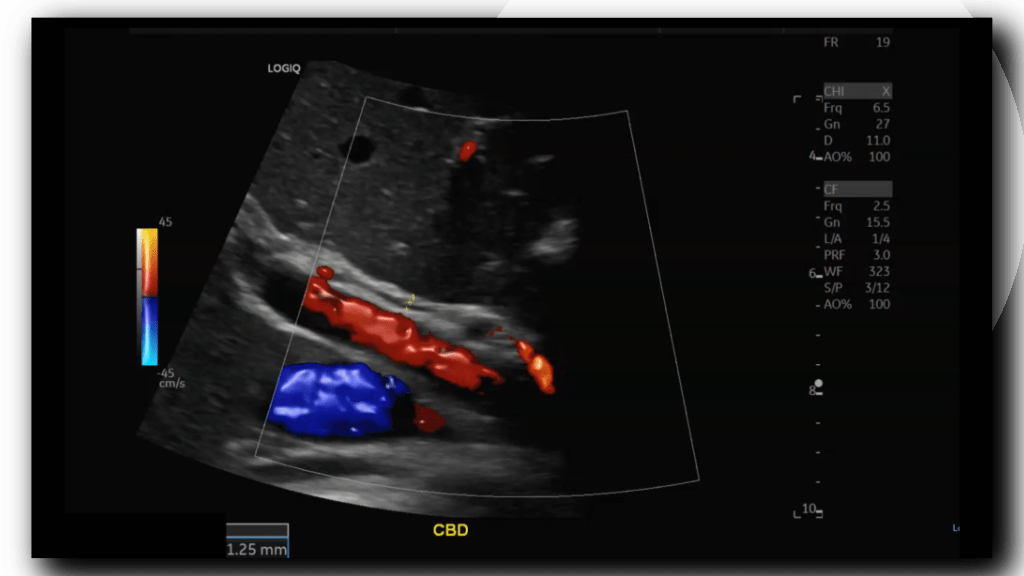

Choledochal cysts are routinely found on ultrasound in infancy, though they can be found on adults and fetal scans as shown below. An anechoic cyst will be present at or before the porta hepatis, size may be variable from small to quite large. In Caroli disease there will be innumerable intrahepatic cysts, this my be difficult to differentiate from polycystic kidney disease (ADPCKD) affecting the liver, typically ADPCKD cysts are non communicating. [3] Once found further imaging and work up must take place to properly classify and treat CC. Endoscopic Retrograde CholanigoPancreatography (ERCP) is the gold standard in diagnosing CC, however Magnetic Resonance CholangioPancreatography (MRCP) is now favored over ERCP due to its non-invasiveness and superior resolution. [5]